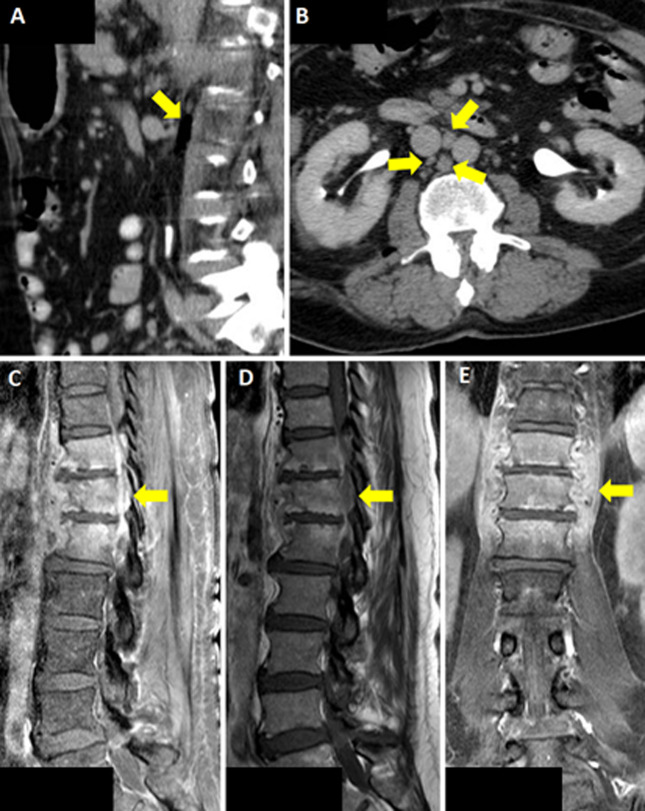

不明原因发热:多药耐药大肠杆菌表现为感染性脊柱炎。

Fever of unknown origin: multidrug-resistant <i>Escherichia coli</i> presenting as infectious spondylodiscitis.

Fever of unknown origin: multidrug-resistant Escherichia coli presenting as infectious spondylodiscitis.